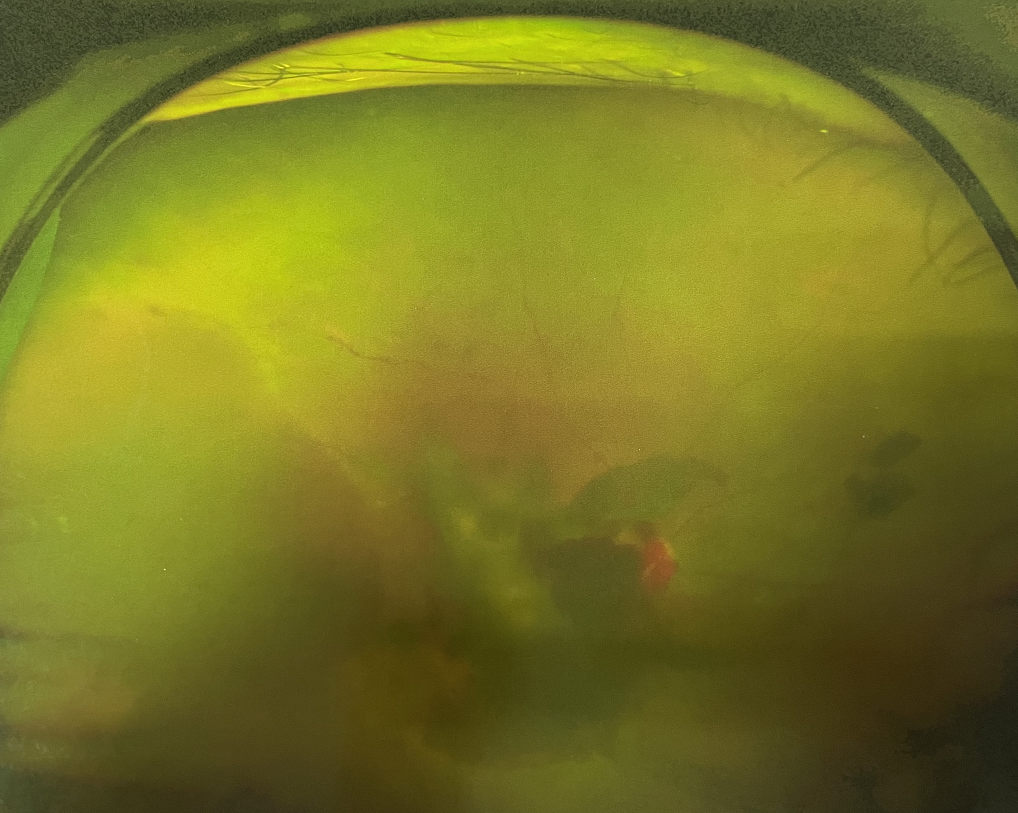

右眼術(shù)前

眼底病??茝埿』⑨t(yī)生檢查后,診斷王女士為“雙眼玻璃體積血、雙眼糖尿病視網(wǎng)膜病變V期”。(V期即5期,纖維增生期,出現(xiàn)纖維膜,可伴視網(wǎng)膜前出血或玻璃體出血。)

張小虎醫(yī)生為王女士進(jìn)行右眼玻璃體腔注藥術(shù),3天后進(jìn)行右眼23G玻璃體切割術(shù)后視力有所提升。

4個(gè)月后王女士來院取硅油,取油后視力恢復(fù)到0.6。“當(dāng)時(shí)來的時(shí)候真的只能看到模糊的影子,特別害怕覺得完了,想說眼睛估計(jì)要瞎了,沒想到手術(shù)后視力竟然提升了,現(xiàn)在也看得比較清楚了。”王女士說到。

張小虎醫(yī)生表示,糖網(wǎng)病進(jìn)展到嚴(yán)重增殖期帶來的視力損傷往往是極其嚴(yán)重的,目前王女士右眼從術(shù)前0.02恢復(fù)到術(shù)后0.6,已屬十分難得。